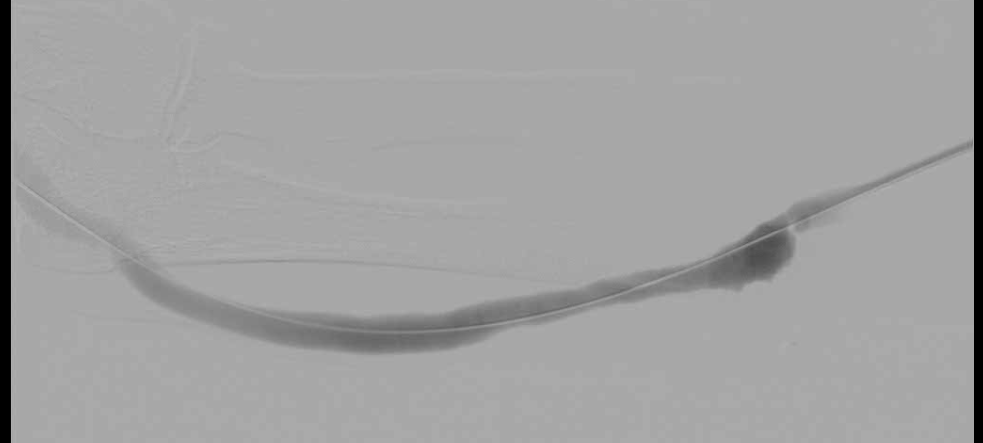

투석혈관 시술

- 투석혈관 협착, 투석혈관 막힘(혈전증) 치료, 투석도관 삽입 및 제거

투석전문의, 신장내과 분과전문의이면서 각종 혈관 시술 1,000례 이상의 경험을 보유한 김철수 원장이 직접 문제 진단 및 시술을 진행합니다.

시술 전

시술 후